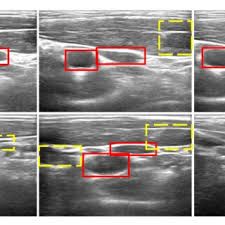

2) 죽상동맥경화증

플라크(지방 덩어리)가 혈관 벽에 형성되어 혈류를 방해합니다. 증상이 없더라도 뇌경색 위험을 높이는 원인이 됩니다.